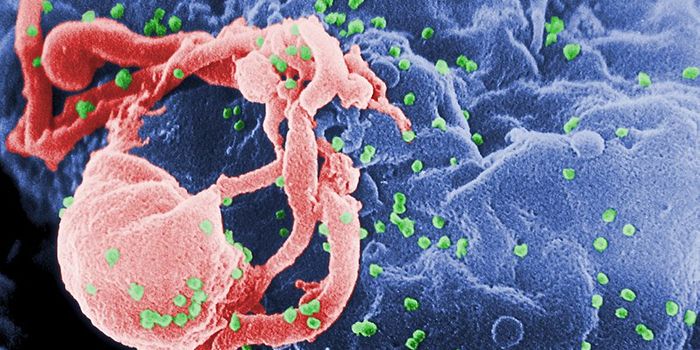

OCT 19, 2017Health & MedicineFor the first time, researchers dare to suggest they may have found a functional cure for HIV, the viral infection that ...

NOV 10, 2019MicrobiologyFor the first time since 2000, researchers have identified a new subtype of HIV.